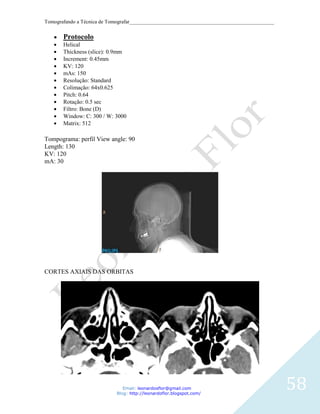

Protocolo

Helical

Thickness (slice): 0.9mm

Increment: 0.45mm

KV: 120

mAs: 150

Resolução: Standard

Colimação: 64x0.625

Pitch: 0.64

Rotação: 0.5 sec

Filtro: Bone (D)

Window: C: 300 / W: 3000

Matrix: 512

Tompograma: perfil View angle: 90

Length: 130

mA: 30

CORTES AXIAIS DAS ORBITAS